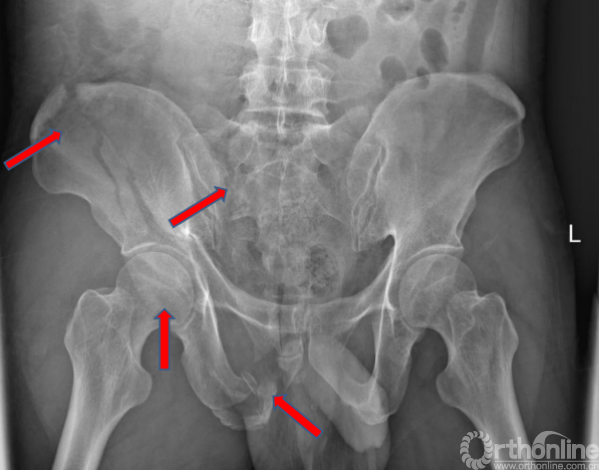

术前X线(2017.09.17)

骨盆正位、骨盆入口位、骨盆出口位